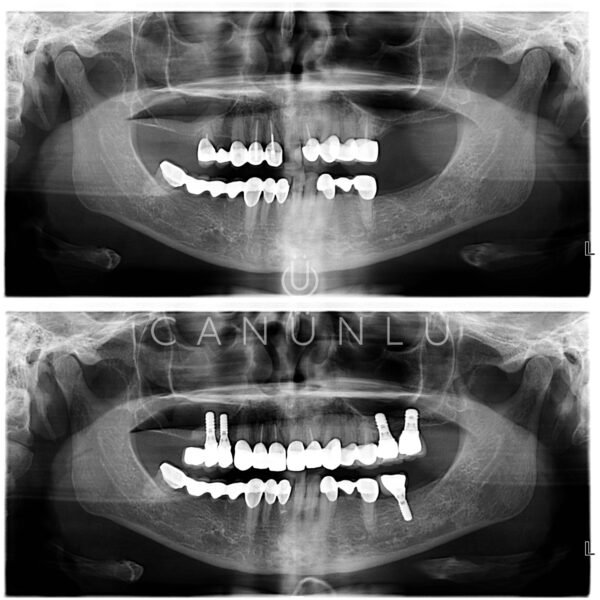

Diş İmplantları, eksik olan dişlerin yerine, çene kemiğine yerleştirilen titanyumdan yapılmış vidalardır. İmplantlar, küçük bir cerrahi işlemle çene kemiğine yerleştirilir. Bu işlemden sonra üç ay gibi kısa bir sürede tamamen çene kemiğine tutunur. Bu tutunma sonrası implant gerçek bir diş kökünün yerini alarak üzerine yapılacak protezi taşımaya hazır hale gelir.

Çene kemiğinin yeterli kalınlıkta ve yükseklikte olduğu durumlarda implant hemen yapılabilir. Çene kemiğinin yeterli olmadığı durumlarda ise bu bölgeye çeşitli işlemler uygulanarak kemik implanta uygun hale getirilir. Hastaların operasyon sonrası ağız hijyenine dikkat etmeleri gerekmektedir.

İmplant operasyonu sonrası protezler ne zaman hazır olur?

İmplant operasyonu sonrası implantın çene kemiğine tam bağlanması 3 ay sonra olmaktadır. Bu süreden sonra implantların üzerine protezler hemen yapılabilmektedir.

İmplantların ömrü ne kadardır?

Günümüzde 30 yılı aşkın klinik takipleri yapılan implantlar bulunmaktadır. İmplant yapılan hasta ağız hijyenine özen gösterirse bu implantları uzun yıllar kullanacaktır